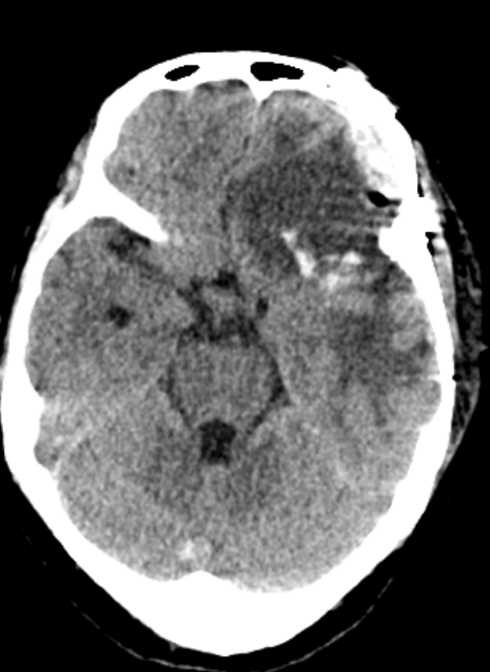

41岁的刘女士,因持续头痛、耳鸣两个月前来就诊。影像检查发现,其大脑深处、紧邻最重要的静脉回流通道——上矢状窦,潜伏着一个直径达7厘米的巨大窦旁脑膜瘤,如同一个“巨型炸弹”。

面对肿瘤巨大、位置深、毗邻重要静脉窦的极高手术风险,神经外科团队凭借精湛的显微手术技术,在错综复杂的血管与脑组织之间精细操作,最终将这枚“霸瘤”完整切除,成功解除了对患者大脑的致命压迫。